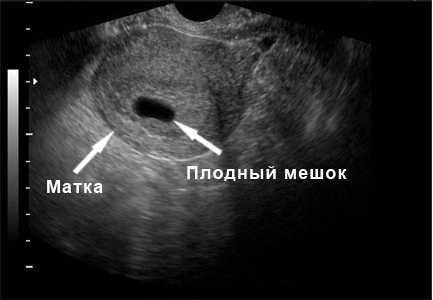

На предложенном снимке определяется 5-я неделя беременности. Хорошо видна матка круглой формы, внутри которой расположен плодный мешок в окружении наполненного кровью и отечного эндометрия. На экране плодный мешок виден, как темный овал с четкими контурами. Он располагается вблизи дна матки, что является одним из самых удобных и безопасных мест. На данном этапе развития размер плодного мешка еще совсем не велик, всего 5-7 мм. Эмбрион уже существует, по внешнему виду он похож на головастика и пока не визуализируется. В сроке 5 недель организуется первичное маточно-плацентарное кровообращение.

Следующее фото представляет собой продольный срез матки грушевидной формы. Небольшой черный овал внутри матки — это беременность в окружении набухшего эндометрия, который вырисовывается контуром более светлых тонов. Эндометрий выстилает внутренние стенки матки, повторяя ее форму и образуя уютное «гнездышко» для будущего «птенца».